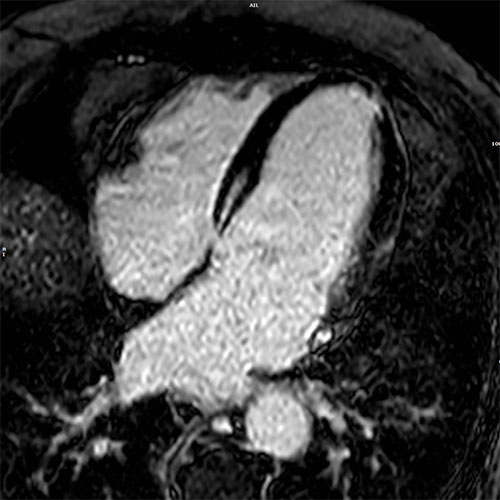

Cardiomyopathy. Cardiac MR images of a patient with non-ischemic cardiomyopathy showing delayed enhancement and severe mitral regurgitation.